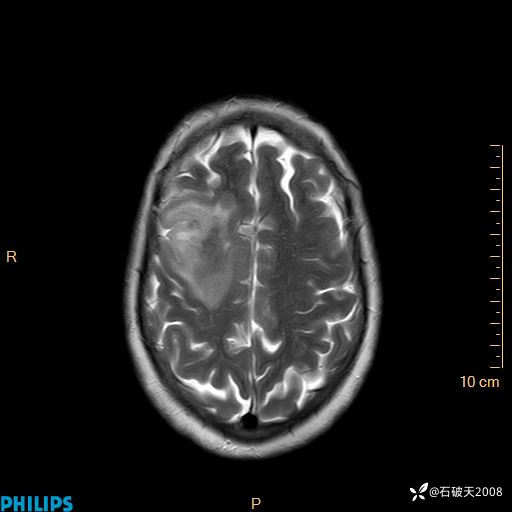

2020.11.14MR

FLAIR